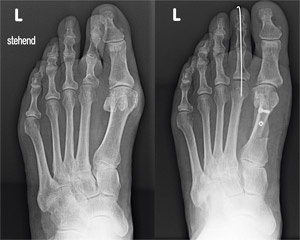

Abb. 1

Röntgenbild vor und nach operativer Hallux-valgus-Korrektur